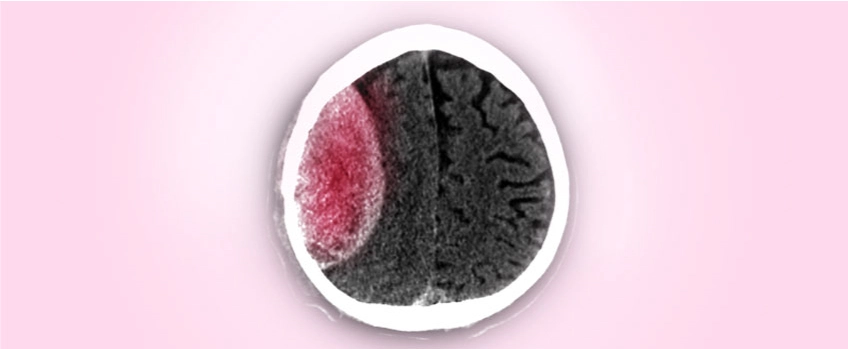

تشخيص الورم الدموي تحت الجافية المزمن يعتمد على الفحص السريري والتصوير الطبي. قد يشمل التشخيص:

1. التصوير المقطعي المحوسب (CT Scan): يعتبر الفحص الأكثر شيوعًا لتشخيص الحالة، حيث يظهر تجمع الدم تحت الجافية.